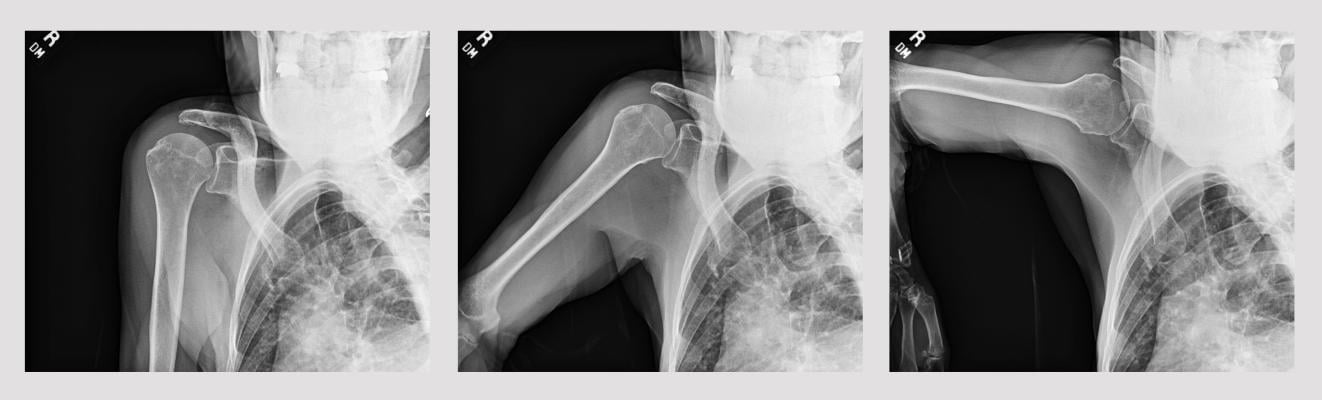

Dr. Hussain’s research evaluated a prototype artificial intelligence (AI) tool developed by Konica Minolta Healthcare for characterizing shoulder dynamics. Seventy-three shoulders (23 normal controls, 41 rotator cuff tears and nine adhesive capsulitis) were imaged using Dynamic Digital Radiography (DDR) and reviewed by two trained readers.

With the DDR image data, Dr. Hussain was able to visualize changes in shoulder pathology and, using the proof-of-concept AI tool, acquire measurements to calculate the scapulohumeral rhythm (SHR). SHR measurement is a time-consuming manual process for calculating the scapulohumeral ratio and evaluating function of the shoulder joint. The new AI tool employs a machine learning algorithm utilizing a convolutional neural network architecture to automate this analysis. Dr. Hussain's research demonstrated that the AI tool has good reliability (ICC 0.58 (95% confidence interval 0.4-0.71)) between manual and AI measurements of SHR.

“We demonstrated the early promise of this AI tool, which may allow for a more rapid measurement of the SHR and enable automated image analysis and diagnostics in shoulder pathology,” says Dr. Hussain. “DDR provides the best of two worlds – it allows us to dynamically visualize the shoulder while it is in motion and enable quantitative measurement of shoulder anatomy in motion, the gold standard for discerning changes in joint anatomy. Further enhancing the prototype AI tool could lead to a more efficient integrations of SHR measurements in clinical workflow and increase the clinical utility of DDR in a clinical setting.”

“One of the really exciting things about DDR is the ability to see what is happening with a patient’s joints from a way that we’ve never been able to see before,” says Dr. Wagner. “In patients with limited range of motion, I can identify the point at which the patient is having difficulty and see the source of the limitations. These insights are especially useful in treatment decisions and pre-surgical planning. For example, in the shoulder, using DDR we can differentiate the limitations in the shoulder vs shoulder blade motion, potentially improving our diagnostic and therapeutic algorithms. New tools that help quantify how structures move in relation to one another only adds to our knowledge of the individual patient so we can deliver the best possible outcome. Although this work and collaboration has already resulted in national and international presentations, publications, and research awards, we are only seeing the top of the iceberg with this technology.”